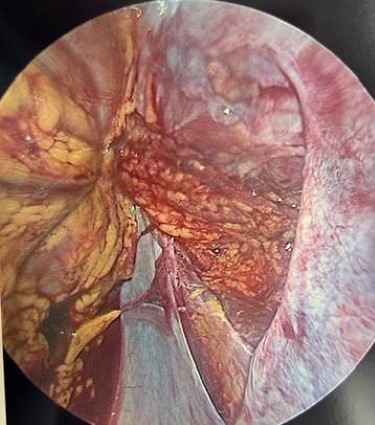

Case 3

A 14-year-old male suffers a handlebar injury to the lower left abdomen after a fall from a bicycle. His vital signs are normal. On physical exam, there is a circular imprint in the left lower quadrant (Figure 1). His abdomen is soft with mild tenderness to palpation. On FAST examination, there is free fluid in the pelvis. Additional images over the area of impact reveal an abdominal wall defect with signs of a traumatic bowel hernia (Video 6). The intestine can be seen crossing the fascial plane into the soft tissue. A CT scan confirms the disruption of the abdominal musculature fascia in the left lower quadrant. The patient requires laparoscopy to identify and repair the defect (Figure 2)

Case 3 shows how detailed imaging can reveal an abdominal wall defect and traumatic bowel hernia, facilitating timely surgical intervention.